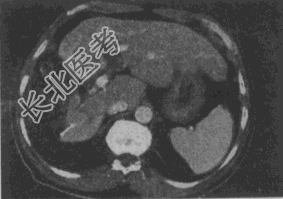

- 单项选择题女,56岁, 腹胀、双下肢水肿、乏力、食欲缺乏,影像所见如下图, 最可能的诊断是

A、酒精性肝硬化并肝血管瘤

B、血吸虫肝硬化并肝癌

C、肝炎后肝硬化并肝癌

D、局限性脂肪肝

E、原发性肝癌